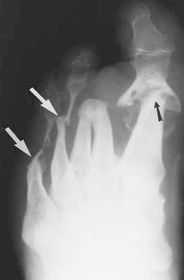

| What disease is this? | Gout |

| What disease is this? What do the arrows indicate? | Gout Arrows = 'punched out' erosions |